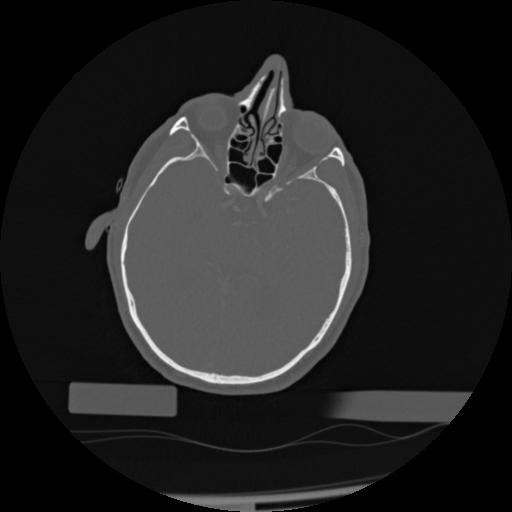

22 ANGIO,CE,Vol,0.5,ANGIO,,